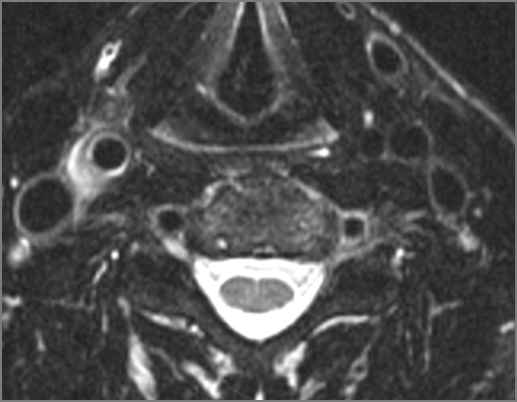

There is edema/abscess within in the prevertebral or paravertebral spaces.

There is erosive process involving the disc spaces or other components of the spine.

There is evidence of thrombus, thrombophlebitis or other occlusive or inflammatory process of the jugular vein or smaller venous tributaries.